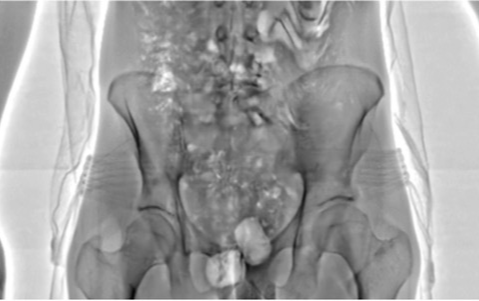

Chỉ sau vài ngày được lắp đặt, những máy quét này đã giúp lực lượng chức năng Anh phát hiện 55 phạm nhân đang âm mưu "tuồn" hàng cấm vào tù. Với sự trợ giúp của máy quét an ninh, các quản ngục có thể lập tức phát hiện các tù nhân lén mang theo vũ khí, điện thoại di động hoặc ma túy, ngay cả khi họ cố che giấu bằng cách... nhét chúng vào cơ thể mình.

Cụ thể, một tù nhân đã bị phát hiện nuốt 4 chiếc điện thoại tí hon vào bụng. Một người khác bị bắt quả tang giấu ma túy trong hai chiếc vỏ trứng đồ chơi của hãng Kinder, sau đó nhét chúng vào cơ thể. Những chi tiết này gần như không thể bị phát hiện trên các máy quét tia X thông thường. Vài tù nhân khác bị cáo buộc lén mang theo USB để liên lạc với bên ngoài, trong khi một số người muốn đem thuốc lá vào tù. Song, tất cả họ đều thất bại trước chiếc máy quét an ninh công nghệ cao vừa được lắp đặt.